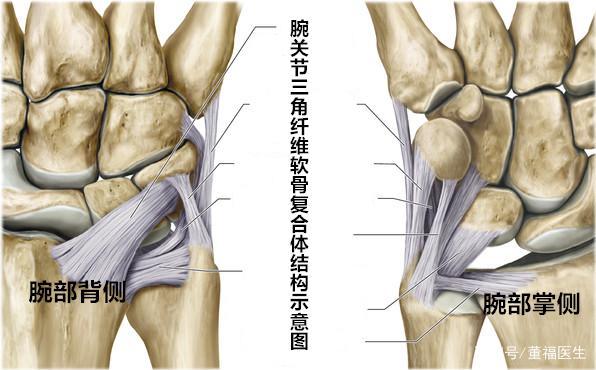

推荐| 三角纤维软骨复合体(tfcc)损伤

三角纤维软骨复合体周围的韧带

三角纤维软骨复合体损伤

三角软骨盘图解

三角纤维软骨盘

三角软骨盘解剖